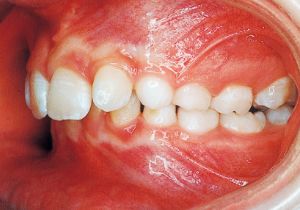

Age at Initial Visit: 11years 3month, Male / Deep bite. Protruding upper bite, Spaced arch.

1 Initial Visit 9-3-’91

Class II deep bite in mixed dentition. A significantly large overjet and a spaced arch are observed. The cephalometric X-ray shows that the anteroposterior displacement of the maxilla and mandible is not particularly large (ANB 5°), but the nasal floor is elevated anteriorly, providing evidence supporting a history of thumb sucking. The skeletal form shows a relatively slight mandibular body deficiency, but the mandibular ramus is adequately sized and appears likely to develop sufficiently. The use of headgear was planned to suppress maxillary anterior growth and achieve relative mandibular advancement. Treatment was performed without extraction, assuming continuity until the permanent dentition stage.